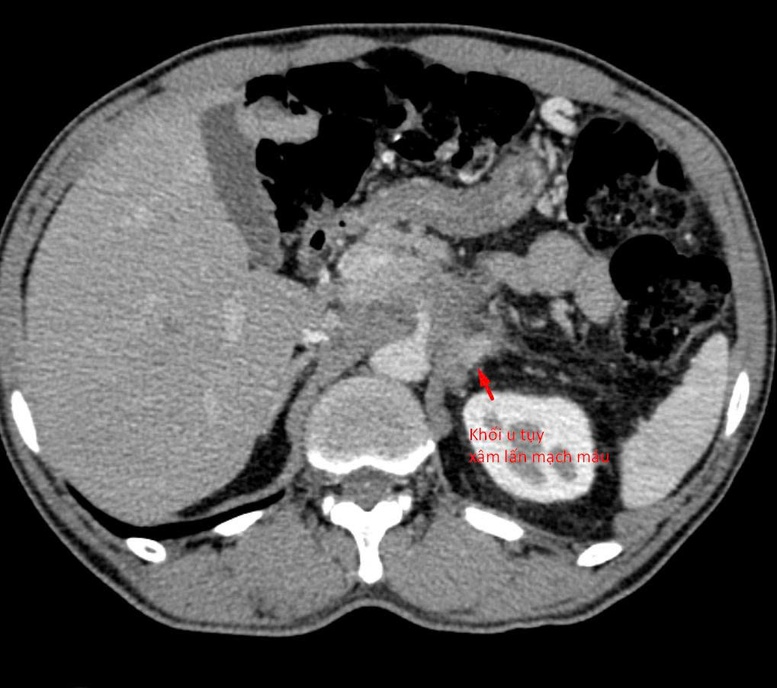

Do nghe mách bảo thiếu cơ sở khoa học, một người đàn ông 64 tuổi, bị u tuỵ xâm lấn mạch máu đã tuyệt thực suốt 3 tuần với hy vọng “bỏ đói” khối u. Kết quả, khối u vẫn còn nguyên, người bệnh sụt 14 kg, thể trạng suy kiệt nghiêm trọng.

Theo lời kể, sau khi thăm khám tại nhiều cơ sở y tế, người bệnh được phát hiện có khối u tụy xâm lấn mạch máu. Tuy nhiên, do chưa xác định được bản chất khối u, bệnh nhân rơi vào bế tắc trong điều trị. Với tâm lý “còn nước còn tát”, người bệnh đi cầu cúng nhiều nơi, thậm chí tuyệt thực suốt 3 tuần với hy vọng “bỏ đói” khối u.

Theo BSNT Trần Văn Giang, khối u tụy nằm ở vị trí đặc biệt phức tạp, tiếp giáp nhiều mạch máu lớn và các tạng quan trọng, do đó cần xác định chính xác hướng vào an toàn ngay từ đầu. Các bác sĩ đã sử dụng chụp cắt lớp vi tính độ phân giải cao để tái tạo hình ảnh đa mặt phẳng, đánh giá chi tiết mối liên quan giữa khối u và các cấu trúc lân cận, từ đó lựa chọn hướng sinh thiết tối ưu.